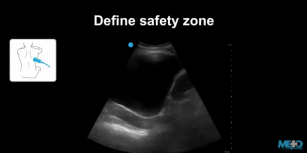

Mastering ultrasound guidance for thoracentesis. 24th Jan 2018 - Sara Damewood, MD Learn how to use ultrasound to guide thoracentesis procedures.